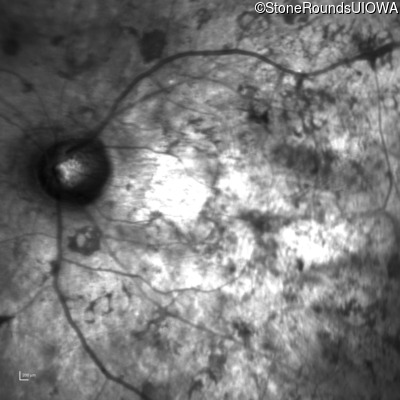

Infrared Fundus Photograph - Right - Hand Motion sc

Exemplar